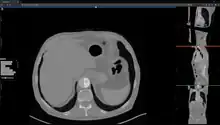

Studierfenster or StudierFenster (SF)[1][2][3] is a free, non-commercial open science client/server-based medical imaging processing online framework. It offers capabilities, like viewing medical data (computed tomography (CT), magnetic resonance imaging (MRI), etc.) in two- and three-dimensional space directly in the standard web browsers, like Google Chrome, Mozilla Firefox, Safari, and Microsoft Edge. Other functionalities are the calculation of medical metrics (dice score[4] and Hausdorff distance[5]), manual slice-by-slice outlining of structures in medical images (segmentation[6][7]), manual placing of (anatomical) landmarks in medical image data, viewing medical data in virtual reality, a facial reconstruction and registration of medical data for augmented reality,[8] one click showcases for COVID-19 and veterinary scans, and a Radiomics module.